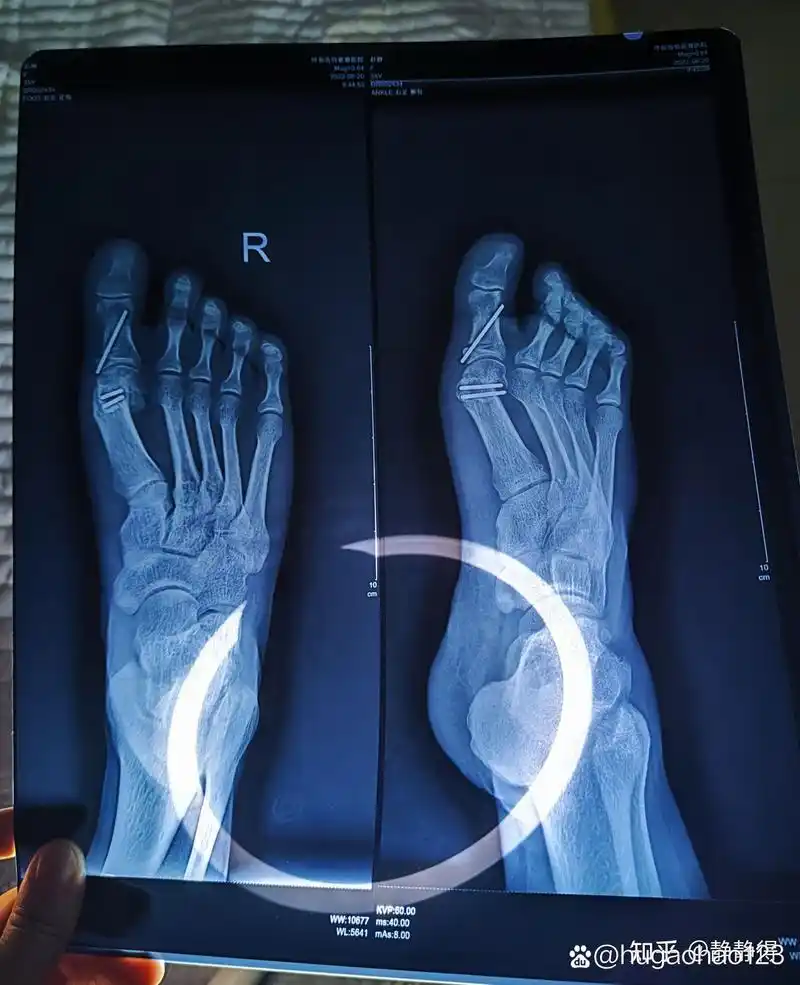

拇外翻(大脚骨)截骨手术后半年

既然是一跖骨偏斜导致了大脚骨,那就需要通过截骨等方式将一跖骨掰直